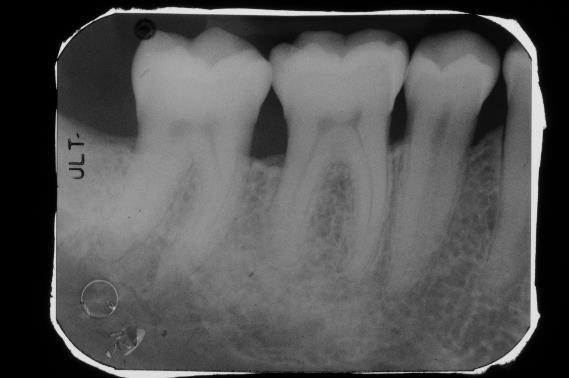

Radiographic view before periodontal regenerative therapy with Straumann® Emdogain®. A deep intrabony defect appeared mesially and distally on the left mandibular first premolar. Pre-surgical probing measured 8 mm. The defect morphology presented as well-contained.